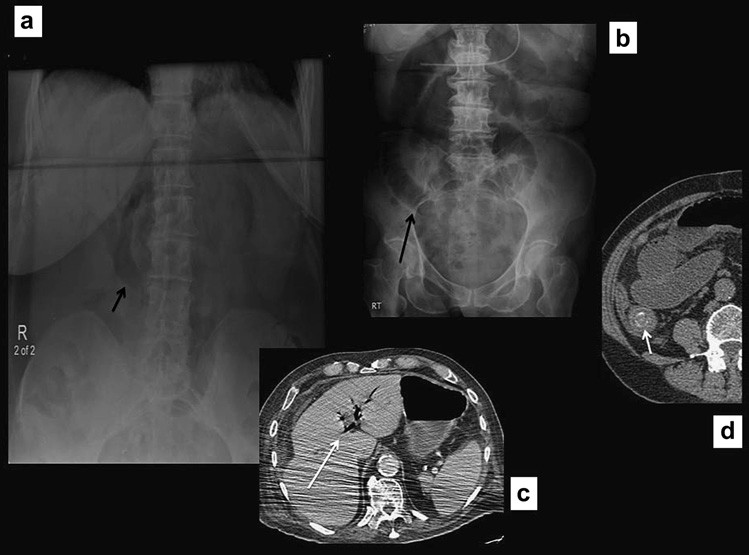

Xoắn manh tràng ít xảy ra so với xoắn đại tràng sigma, chỉ chiếm dưới 5% các trường hợp tắc đại tràng. Xoắn thường ở những người trung niên, điển hình là những người không có tiền sử phẫu thuật ổ bụng. Xoắn ở đại tràng lên, vị trí điển hình là ngay trên van hồi-manh tràng. Phim X quang bụng thường cho phép chẩn đoán và cho thấy quai ruột giãn to kéo từ hố chậu phải đến góc phần tư trên trái ổ bụng. Ruột non thường giãn và đại tràng ở đầu xa bị xẹp. Chụp cắt lớp vi tính hiếm khi được yêu cầu để khẳng định chẩn đoán, nhưng mục đích để phát hiện mạc treo bị xoắn và đoạn ruột bị thiếu máu hoặc thủng (Hình 5).

Hình 5. Xoắn manh tràng (a) Phim X quang bụng đứng thấy một quai ruột giãn nhô vào góc trên trái ổ bụng. Lưu y không có khí trong các đoạn đại tràng, các quai ruột non giãn to (b, c) Chụp CT xác định xoắn manh tràng, cũng thấy hình “mỏ chim” của mạc treo manh tràng xoắn.